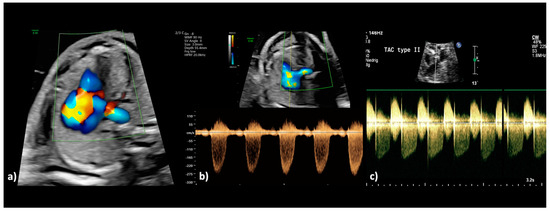

Figure 1.

(a,b): Truncus arteriosus type 1 at 31 + 4 weeks. (a) Perimembranous outlet VSD as interventricular communication with the broad common arterial trunk in the overriding position. (b) In the color Doppler mode, the filling of the common arterial trunk from both ventricles and the posterior branch of one pulmonary artery can be seen (aortic dominance); aliasing or a high variance, which indicates a stenosis of the truncal valve, is not present.

(a,b): Truncus arteriosus type 4 with interrupted aortic arch type b at 23 + 5 weeks. (a) The 2DE shows the ventricular outlet part with the overriding common trunk, the truncal valve as well as the wide truncus pulmonalis and the hypoplastic ascending aorta (pulmonary dominance); (b) The color Doppler mode shows the outflow from both ventricles into the common arterial trunk and further into the pulmonary trunk as well as into the hypoplastic aorta.

Figure 4.

(a–c): Truncus arteriosus type 1 at 22 + 0 weeks. (a) In the color Doppler mode, the filling of the common arterial trunk from both ventricles and the confluent origin of both pulmonary arteries from the posterior side of the aorta is visualized (aortic dominance), as well as aliasing and high variance as indications of disturbed blood flow due to stenosis of the truncal valve. (b) The spectral Doppler examination confirms the presence of a stenotic truncal valve by a high maximum velocity (peak systolic velocity: 3.0 m/s; maximum pressure gradient (ΔPmax: 36 mm Hg) and wide variation of the blood flow. (c) In another fetus with truncus arteriosus type A2 at 34 + 1 weeks, there is both a relevant stenosis and a severe regurgitation of the truncal valve; during systole, the tubular antegrade flow with a peak velocity of 2.40 m/s can be recognized; during diastole, the insufficiency of the truncal valve with a peak velocity of 3.30 m/s can be recognized.